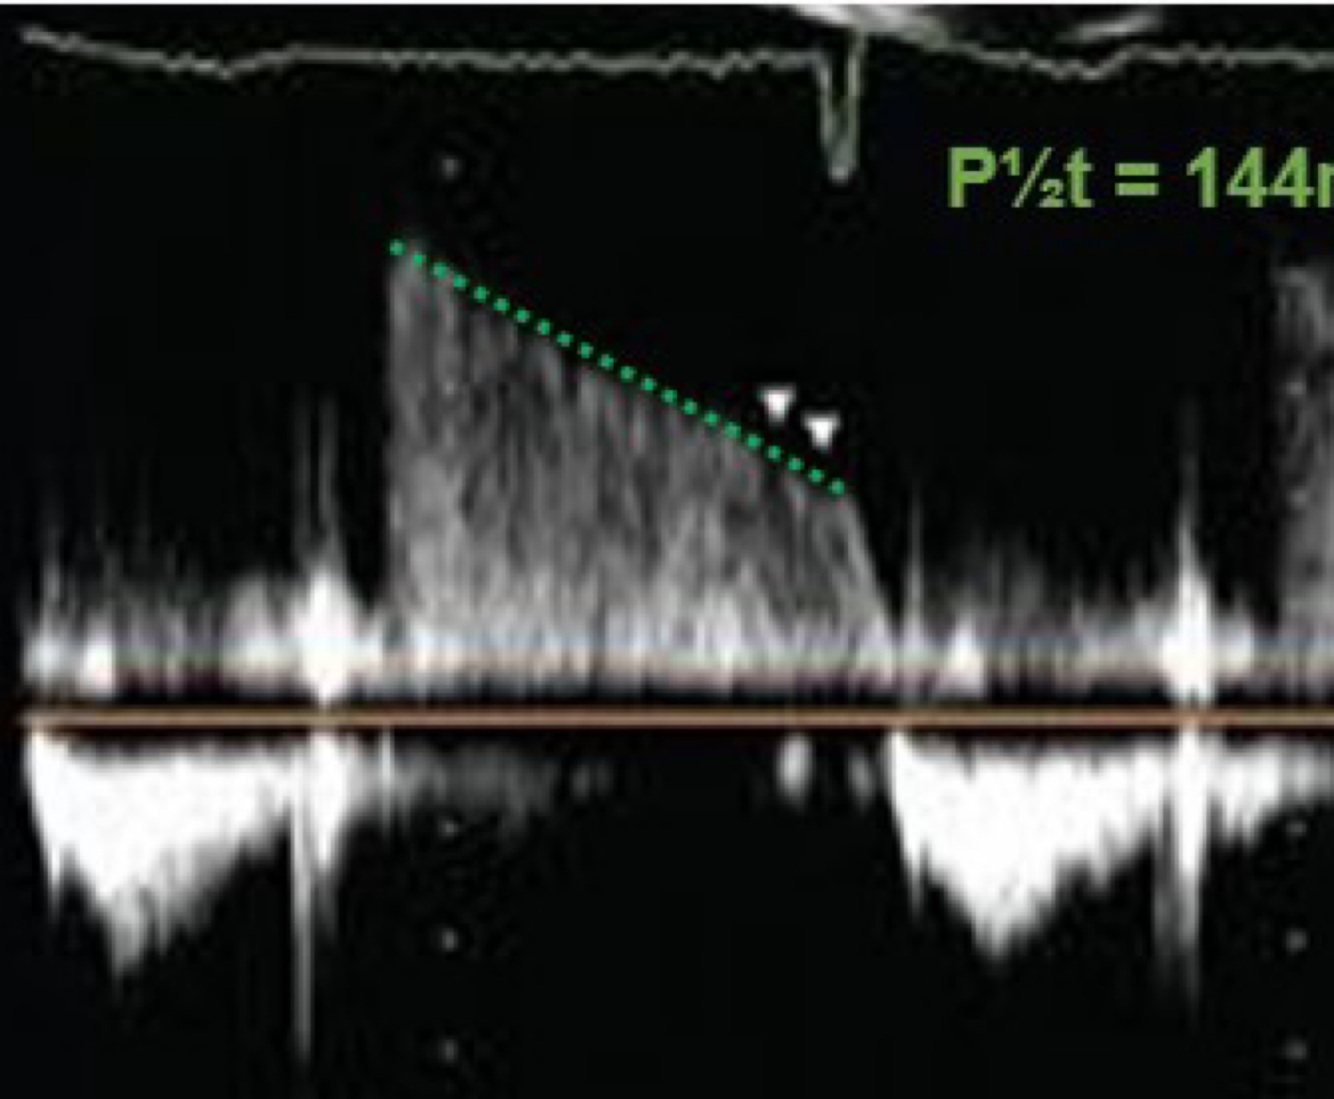

Q

Grade the PR severity in this image based on the pressure half time

A

Moderate

Mod >100 mesic

Sever <100msec

What is the MVA given the pressure have time in this image. What is the grade of stenosis does this correspond to?

1.58 cm2 and this is mild *Mild >1.5*